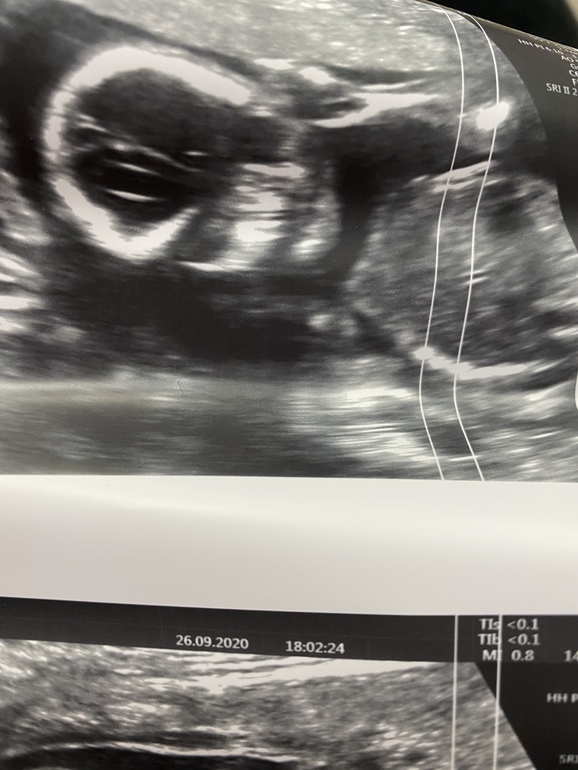

УЗИ, КТГ, доплерВсем привет ходили сегодня на скрининг платный всё слава богу хорошо весим 208 гр лежит поперёк не сильное предлежание плаценты сказал подняться должна.А самое главное у нас девочка🥰🥰🥰посмотрите это же точно?Мамы девочек у вас такие же пирожки?

Я пока разобрала, где попец, а где девчачьи прелести, телефон по часовой и против часовой стрелки несколько раз перевернула)). Она, не сомневаетесь